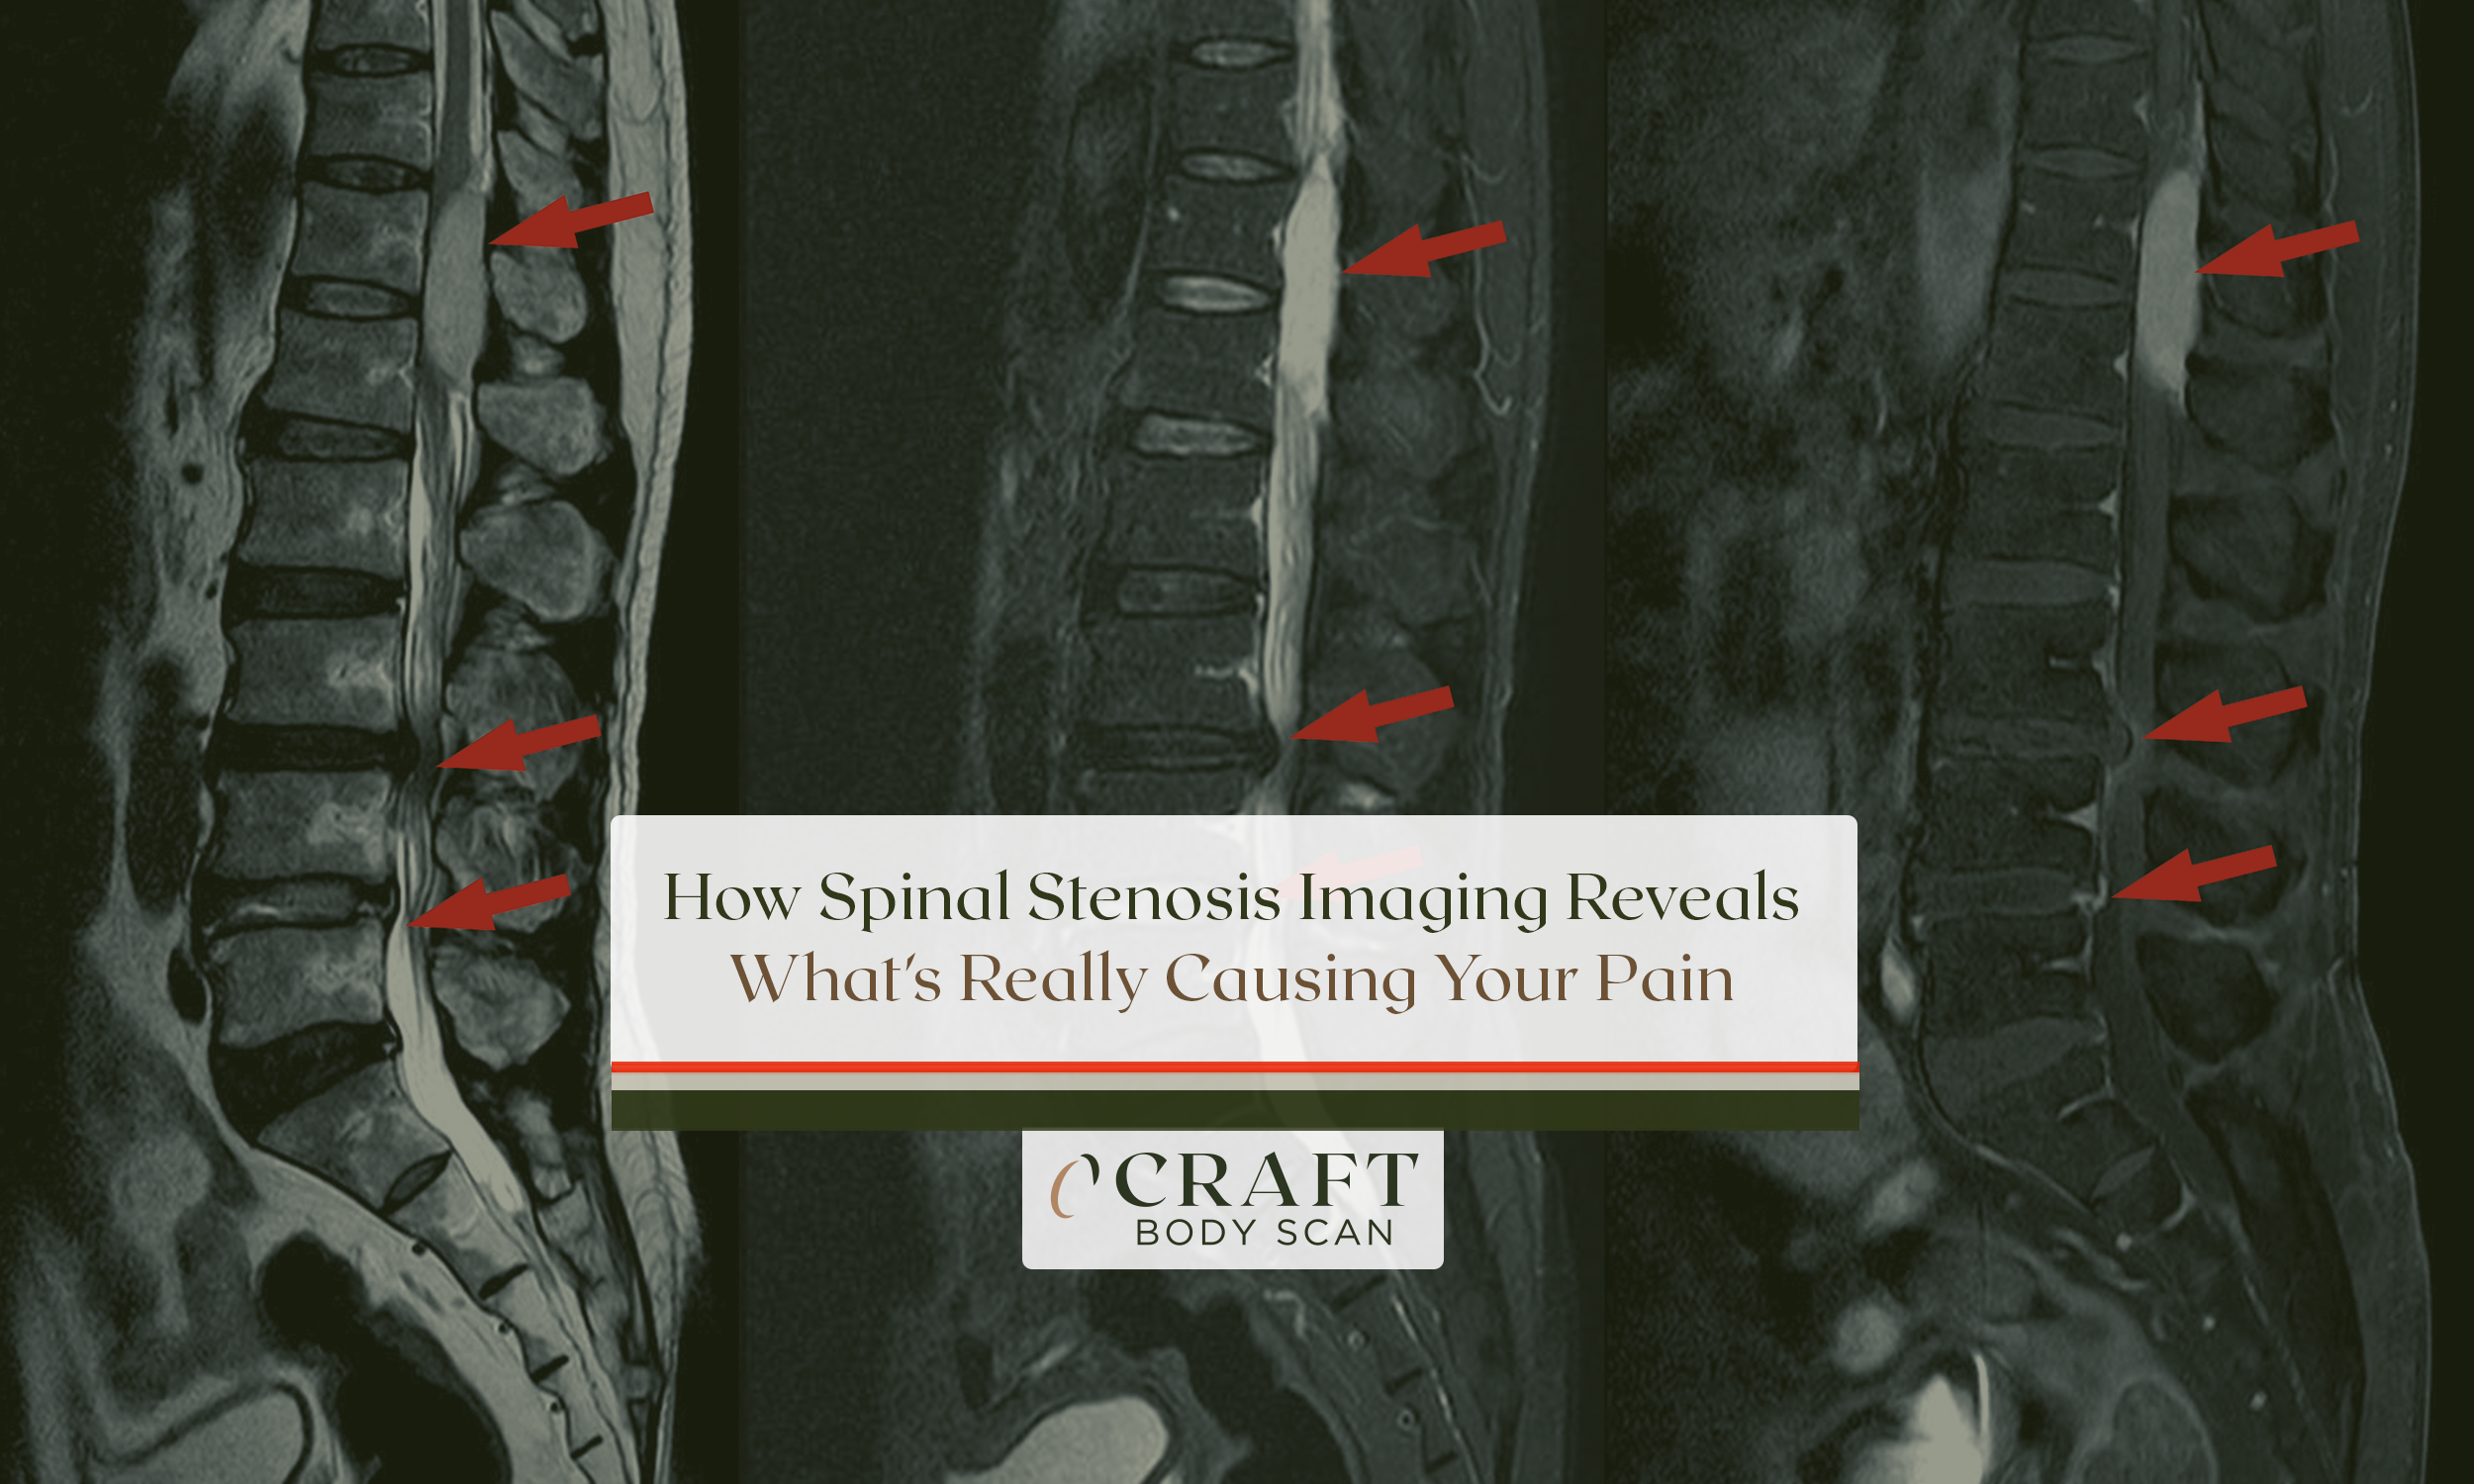

A lumbar MRI for sciatica uses powerful magnetic fields to create detailed cross-sectional images of your lower spine. These images reveal herniated discs, bone spurs, and inflammation pressing against nerve roots.

Herniated disc material appears bright on T2-weighted images. Nerve roots show intermediate signal. Bone appears dark due to low water content.

These signal differences reveal compression patterns doctors use to guide treatment. The scanning sequences capture multiple views taking 3-5 minutes each.

Radiologists examine hundreds of image slices from multiple angles. Sagittal views show disc alignment and herniation extent on lumbar MRI for sciatica.

Axial views reveal nerve root compression severity. Coronal views detect lateral abnormalities affecting nerve exit holes.

Lumbar MRI for sciatica shows exactly which nerve is compressed and how severely compressed it appears. Radiologists grade compression using standardized systems that directly guide treatment decisions.

Grade 1 means the nerve root contacts disc material but maintains normal shape. This often improves with conservative treatment protocols.

Grade 2 means the nerve root is displaced or deformed by compression visible on lumbar MRI for sciatica. These patients typically need more aggressive intervention approaches.

Grade 3 means the nerve root is severely compressed and difficult to visualize on the scan. These cases often require surgical decompression for symptom relief.